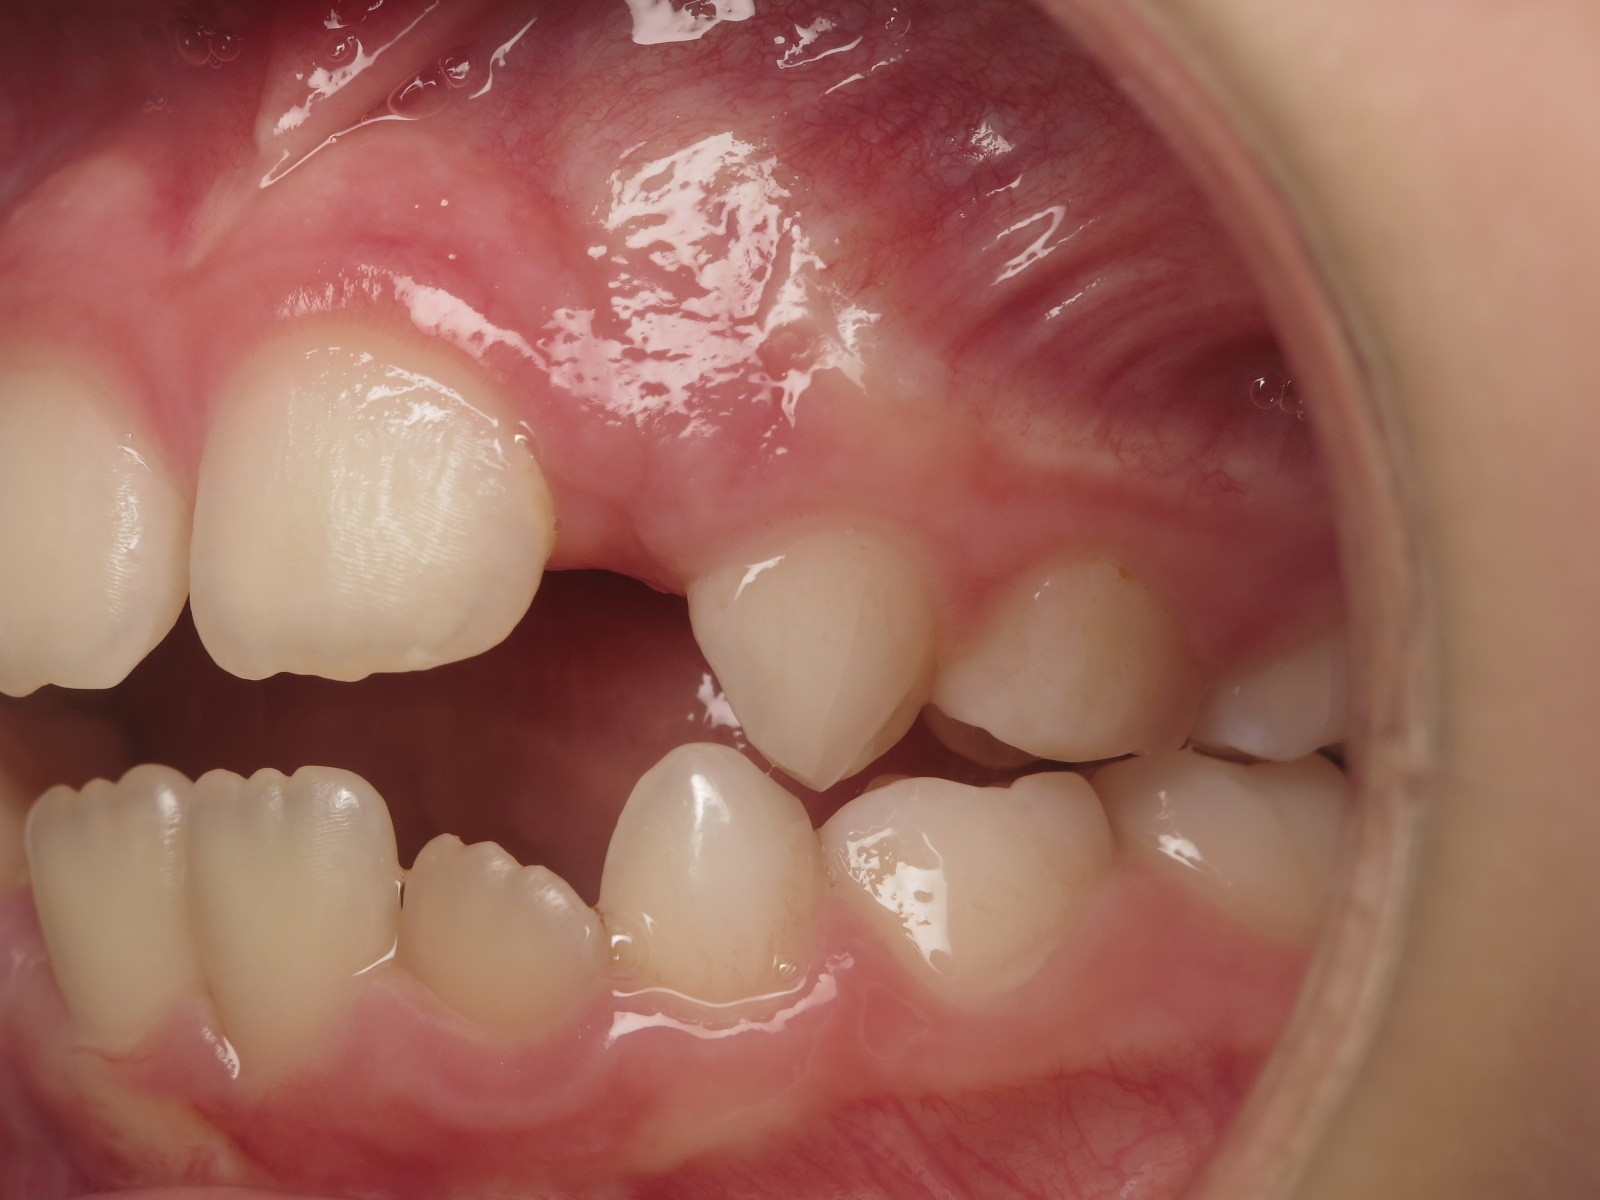

appareillage mobile pendant 5 mois

surveillance évolution de la dentition pendant 27 mois